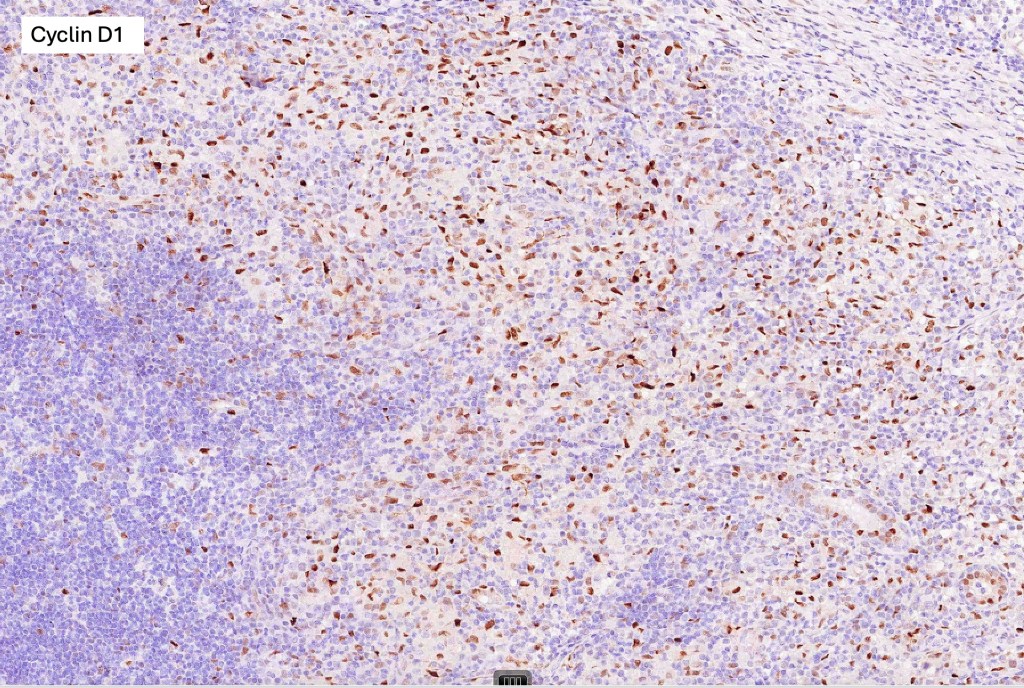

Histological features

•Large cell transformation occasionally present